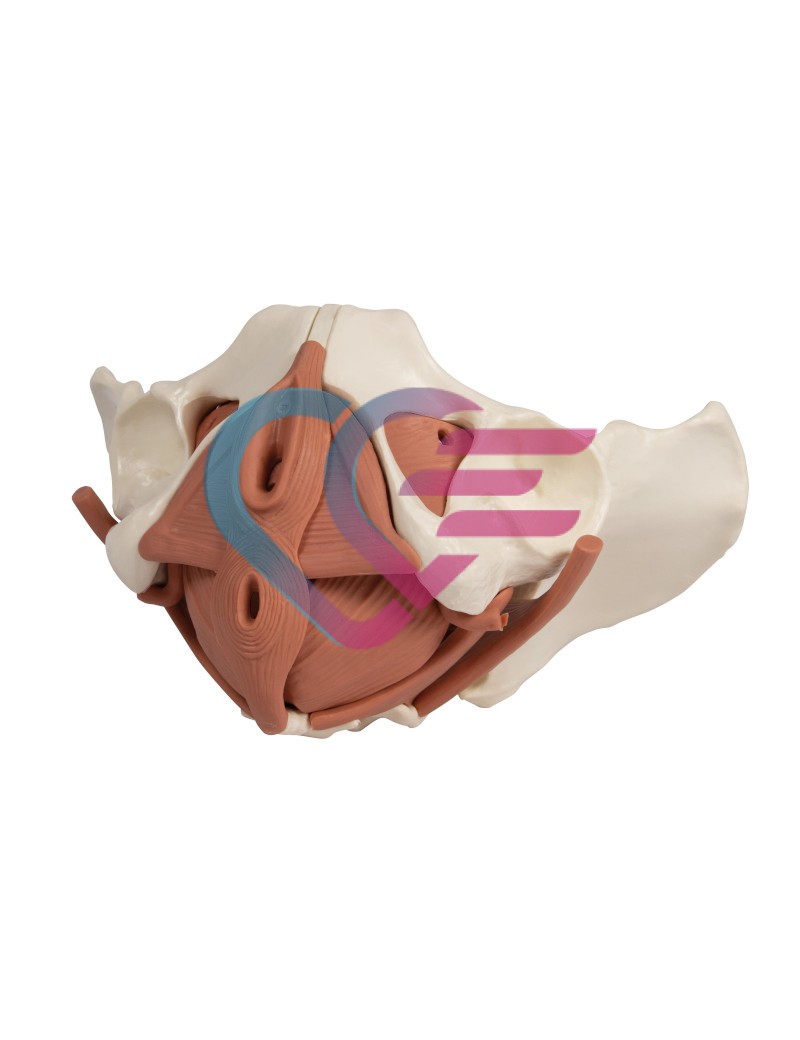

- Poboljšani model dna ženske zdjelice predstavlja zdjelično dno u njegovim slojevima.

- Sastoji se od 12 dijelova.

- Idealan model za tečajeve pripreme za porod, edukaciju primalja, tečajeve vježbi za zdjelično dno ili jednostavno za anatomske studije zdjeličnog dna.

- Sadrži također 2 kosti kuka i križnu kost.

- Mišići su povezani magnetima što omogućuje njihovo jednostavno uklanjanje radi demonstracije slojeva.

- Prikazani su sljedeći mišići koji se mogu ukloniti:

– musculus obturatorius internus (lijevi i desni)

– musculus piriformis (lijevi i desni)

– musculus coccygeus (lijevi i desni)

– diaphragma pelvis

– urogenitalna dijafragma

– sfinkteri urogenitalnog i digestivnog trakta.

- Dimenzije: 27 x 18 x 17 cm.

- Težina: 960 g.

- Proizvedeno u Njemačkoj.